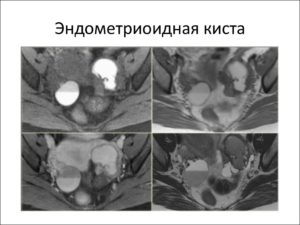

МРТ таза. Эндометриоидная киста правого яичника с равномерно гипоинтенсивным сигналом.